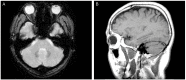

A 32-year-old man with blurred vision in the right eye and headache presented with anterior uveitis, an intraocular pressure (IOP) of 60 mmHg, an open angle, no visual field defects, and normal optic nerve. He had a history of five previous similar attacks. In each of the previous instances, his anterior uveitis and high IOP were controlled with antiglaucoma medications and topical steroids. However, at the fifth attack, his optic disc was pale and a superior paracentral visual field defect was shown. Brain magnetic resonance image studies were normal. This case represents that a recurrent Posner-Schlossman syndrome (PSS)-induced optic disc atrophy likely due to ocular ischemia caused by a recurrent, high IOP. Although PSS is a self-limiting syndrome, we should manage high IOP and prevent ischemia of the optic nerve head by treating with ocular antihypertensive medications.